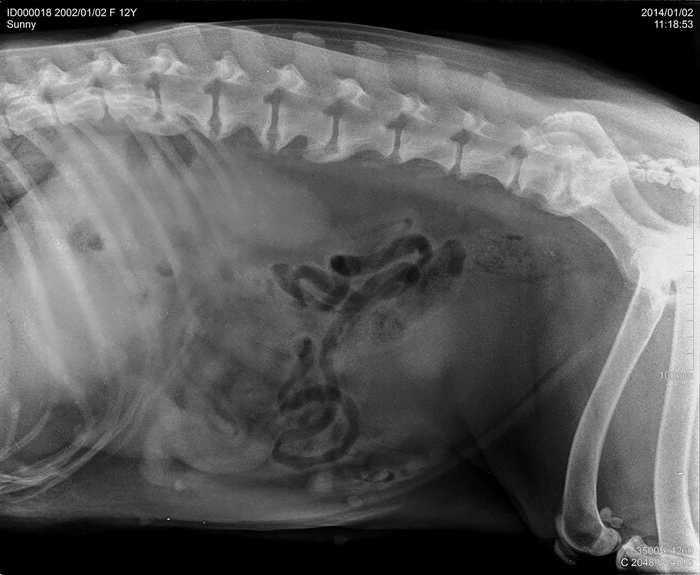

Úvod > Galerie > RTG snímky